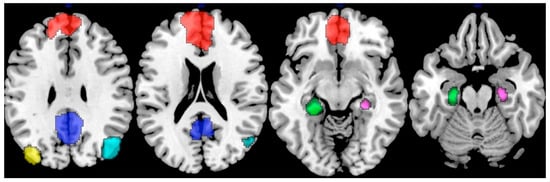

Various individual-specific factors such as age, sex, environmental experience, genetics, independent of levels of Aβ and tau, affect the pathological progression [32]. This heterogeneity of the neuropathological features encourages investigation of personalized biomarkers that provide evidence to distinguish different preclinical/clinical stages. One such promising biomarker is the whole-brain functional connectivity pattern, which can be derived from electroencephalography (EEG), magnetoencephalography (MEG), and functional magnetic resonance imaging (fMRI). In EEG/MEG studies, connectivity is typically assessed by examining signal synchrony or coherence between brain regions within specific frequency bands [33], reflecting fast neural communication. In contrast, fMRI-based connectivity is quantified using correlations between regional Blood Oxygen Level-Dependent (BOLD) signals, providing spatially detailed mapping of large-scale network organizations. Throughout this review, we use the term “connectome” to refer to the fMRI-derived whole-brain functional connectivity and examine its alterations across the Alzheimer’s disease spectrum. The connectome encompasses several major functional networks, such as the default mode network (DMN, Figure 3), which supports internally directed cognition and memory processes [34]; the salience network (SN), involved in detecting and integrating relevant internal and external stimuli [35]; and the frontoparietal network (FPN), which underlies executive control [36]. FC metrics capture such network organizations by quantifying temporal correlations between the BOLD signals of different brain regions. Large-scale networks are typically identified using data-driven approaches like independent component analysis (ICA) [37] or voxel-wise clustering [38], which group together brain regions showing highly correlated activity patterns.

Figure 3.

Nodes representing the default mode network (DMN). The highlighted regions include the medial prefrontal cortex (mPFC; red), posterior cingulate cortex (PCC; blue), left inferior parietal lobule (yellow), right inferior parietal lobule (cyan), left hippocampus (green), and right hippocampus (purple), each serving as a node contributing to the network’s functional integration. Adapted from ref. [54] under Creative Commons Attribution License (CC BY).